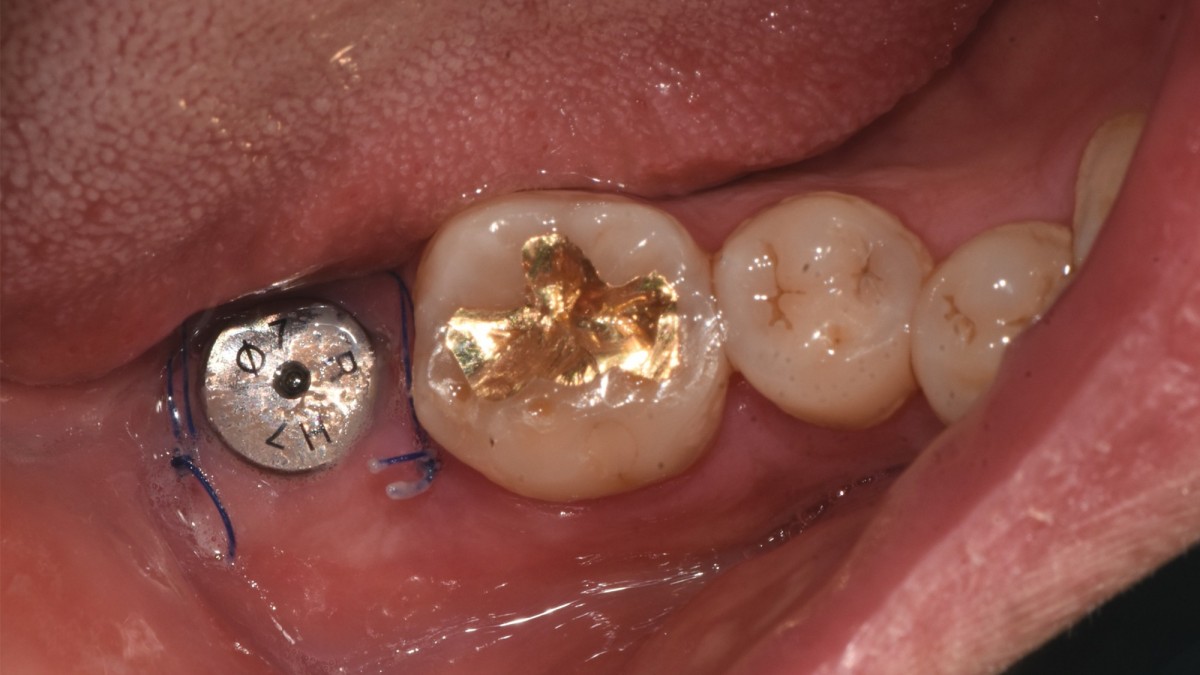

Single implant (staged) Arum NB1, f/u

A 47-year-old male patient had a crown with an ill-fitting margin and crack-tooth syndrome in the lower 2nd molar. No systemic issue.